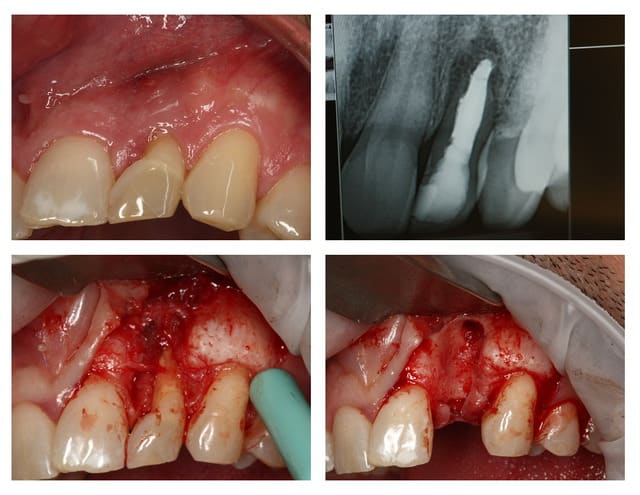

Cas clinique :

Exo de la 22 et ROG important fait il y 5 mois

Mineros et membranne collagène (pas de photo, sorry)

Résultat de la greffe sympa, le nonos est bien solide.

La gencive bof...

Je décide de faire un conjonctif en même temps, histoire de m'amuser un peu.

Suture pour tracter le greffon en place, puis fermeture.

PS le patient ne désirait pas de provisoire !

Joli joli, mais tu n'as pas une RX, ton premier forage semble aller dans la 21...

Oui, j'ai pris des radio, et je me suis replacé après le foret de 2.0 mm !

Il y avait une fistule, donc j'ai du disséqué en 1/2 épaisseur le lambeau vestibulaire pour elliminer tout ce tissus malsain attaché à la dent et à l'alvéole.

Pour pouvoir nettoyer l'os au max, et ne laisser aucune trace du tissus de granulation, j'ai besoin d'accès mécanique (CA + fraise) et visuel.

Le cas de la 22 présenté, ce fut 60 minutes total pour la pose de l'implant et la greffe conjonctif.